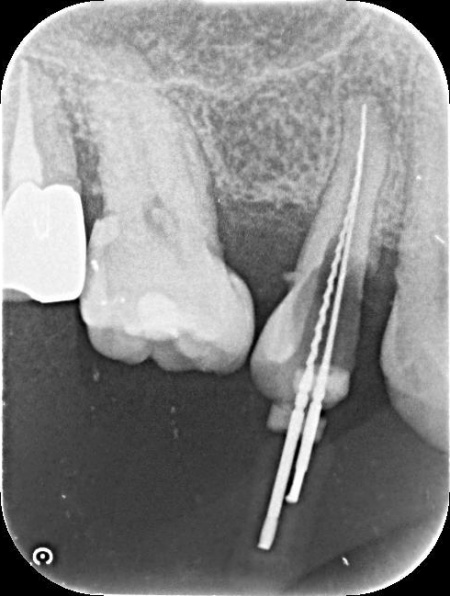

レントゲン撮影で詳しく検査した結果、虫歯が神経まで進行しており、歯根の先に黒い影が確認できます。

この影は慢性歯根膜炎と呼ばれ、虫歯による感染が神経にまで及び、歯根の先にある歯根膜という組織に炎症が起きている状態です。

まず、根管治療で神経を慎重に取り除き、根管内の清掃と消毒を行います。

その後、細菌の侵入を防止するために、歯や体になじみやすいセメント材料「MTA」を用いて、根の内部を密封しました。